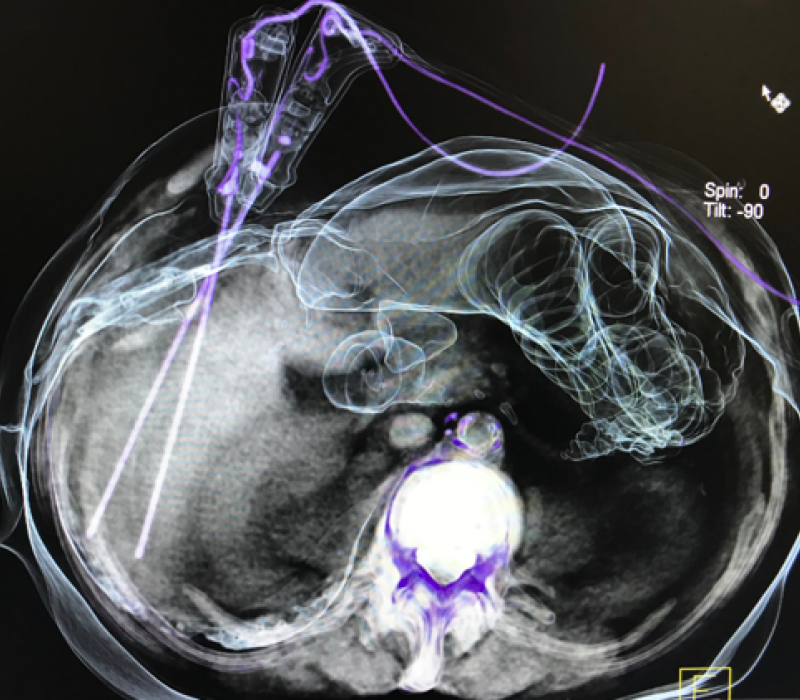

Experience with Angio-CT for Interventional Oncology

Interventional oncology therapies include a wide range of options in which imaging is a crucial factor for success. Imaging solutions play a key role in assessing planning, guiding and controlling the results during oncology procedures.